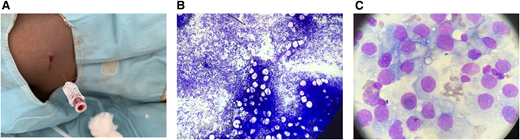

Standardizing blood film staining

The majority of blood films (BFs) were previously characterized by poor uptake of basophilic dye which resulted in unsatisfactory staining of white blood cells making them unidentifiable (Figure 3A). The BFs were also subjected to poor smear techniques and water artifacts. BF tracking was not possible because of inadequate labeling, absence of accession numbers, and lack of storage. Several weeks’ worth of troubleshooting resulted in a new standard operating procedure (SOP) that was designed specifically for our laboratory, and it included improved staining procedures (Figure 3B-C) that were incorporated into a comprehensive Microscopy Manual. Previously, BF staining showed significant variation in staff technique and practice because there was no SOP. Because previous BFs had not been stored, a formal comparison between previous BFs with those from current practice was not possible. Review of the most recent group of stored slides (from May and part of June 2019) showed satisfactory staining in 42 of 42 slides.

Stained sample slides and staining procedures. (A) The staining process failed because of poor uptake of basophilic dye by white blood cells. (B) Laboratory staff assessing a variety of staining protocols. (C) Successful staining of a lymphocyte (the pediatric patient was unexpectedly found to have falciparum malaria).

Stained sample slides and staining procedures. (A) The staining process failed because of poor uptake of basophilic dye by white blood cells. (B) Laboratory staff assessing a variety of staining protocols. (C) Successful staining of a lymphocyte (the pediatric patient was unexpectedly found to have falciparum malaria).